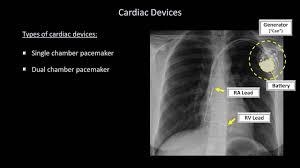

How To Interpret A Chest X Ray Lesson 9 Atelectasis Lines Tubes Devices And Surgeries Youtube